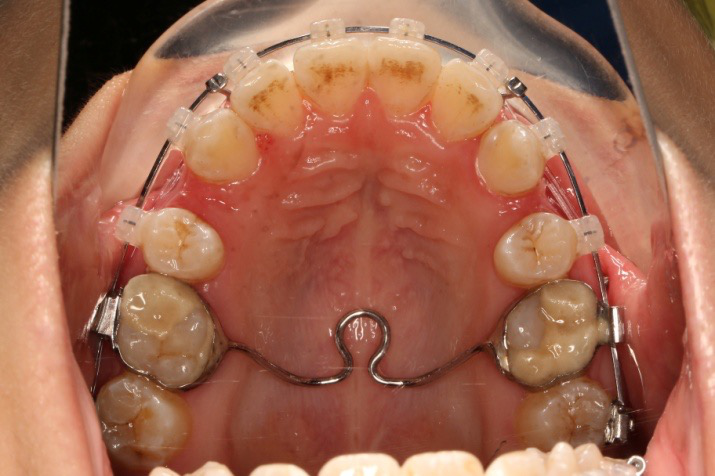

2018.5.25  (19个月)拆TPA,16、26粘tube 上颌0.14*25cu-niti  下颌0.018*25niti2018.7.23  上颌 0.017*25TMA,下颌0.017*25ss43压低曲,双侧后牙垂直牵引

2018.09.29  15、43、16、17、11、21重粘,上0.016*25cu-niti 下0.018niti 上连扎

上后牙:高度保持不变/压入性移动,尽量避免伸长;▲垂直向控制中,应防止上后牙颊侧倾斜(TPA);▲腭尖高度控制也重要。

长时间使用TPA或者使用颌内支抗关间隙,容易造成第一磨牙和第二磨牙颚侧尖出现台阶,容易造成术后早接触及咬合关系不良